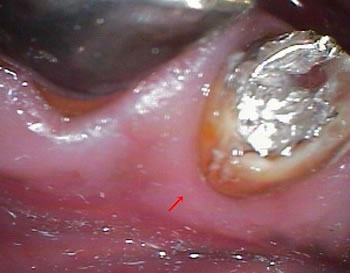

やはり歯根に亀裂(矢印の延長です)が見られますね、、、

そっと金属の土台を外しますと、、、 |

やはり亀裂(赤い矢印)が根の先まで続いております!

レントゲンでの「亀裂みたい?」はやっぱり本当だったのですね!

真っ2つではありませんが、根の先まで亀裂(クラック)が入っていたのです!

歯の根が割れていると感染根管治療ではなく、

治療方法は抜歯に、、、 |

こんな感じに真っ2つに割れる寸前だったのでした!